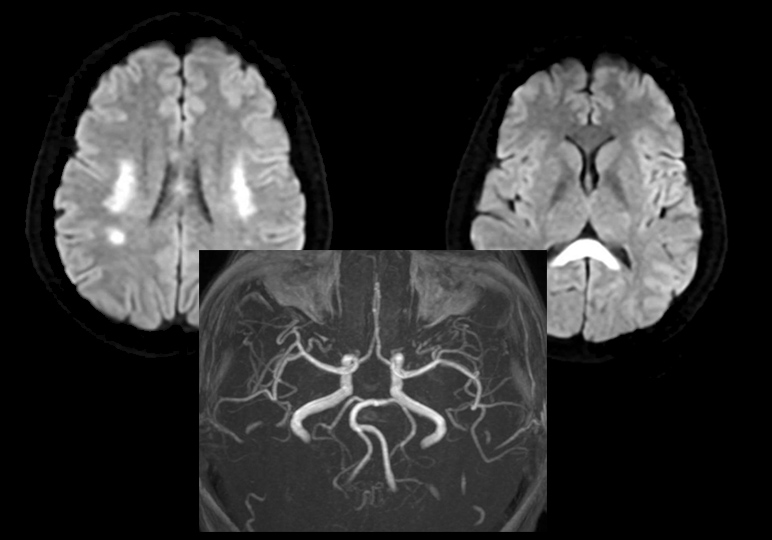

Đột quỵ ở phụ nữ sau IVF: Khi can thiệp sinh sản trở thành yếu tố nguy cơ tiềm ẩn

Không có tiền sử đột quỵ, không bệnh nền tim mạch, một phụ nữ 42 tuổi bất ngờ nhập viện vì nói đớ sau khi thực hiện thụ tinh trong ống nghiệm (IVF).